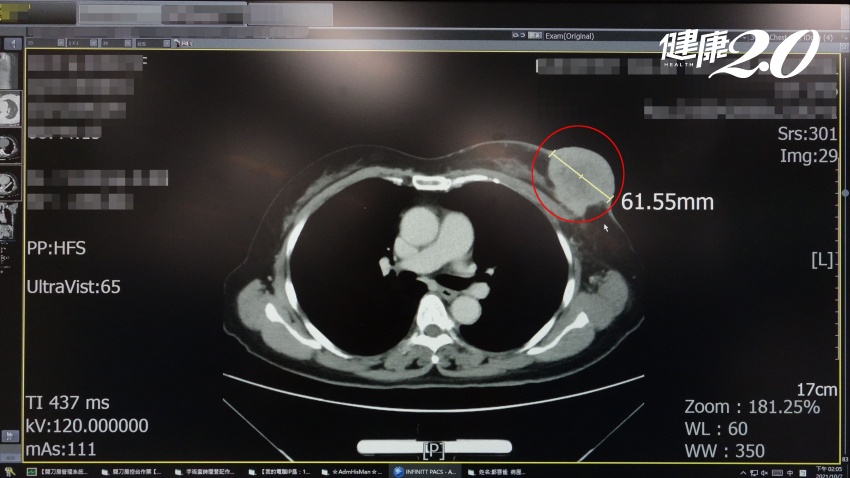

55歲的陳女士就醫時,乳房腫瘤已經長到比乒乓球大,並且擴散到皮膚表面,造成乳房大面積破皮損傷。大林慈濟醫院一般外科醫師邱郁婷說,病患自述摸到乳房腫塊已有1年多的時間,測量其腫瘤擴散到皮膚的面積很大,約有12公分。安排超音波檢查,也因腫瘤過大,超音波探頭無法正確估量乳房內腫瘤的體積,且其腋下淋巴結已嚴重擴散,評估為第4期乳癌。

所幸陳女士很幸運,對化療的反應很好,做第2次化療時,她突出的腫瘤幾乎完全消平,腋下淋巴結也縮小許多。但因她化療前的腫瘤實在太大,而且腫瘤距離乳頭又近,邱郁婷然擔心腫瘤細胞可能藉由乳頭擴散到乳房其他部位,因此建議陳女士接受乳房全部切除手術。